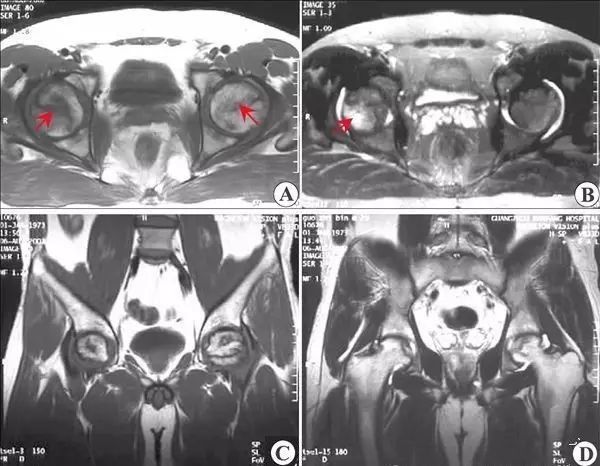

股骨头坏死的 MRI 表现

MRI 敏感性优于骨核素扫描和 CT 及 X 线检查。这是因为股骨头发生坏死后,修复组织不断伸入坏死区上方骨髓的变化早于骨质变化,MRI可以在骨质塌陷及修复以前反映出骨髓细胞的变化。所以, MRI 应作为早期检查诊断骨坏死的主要手段。

I 期 股骨头不变形,关节间隙正常,X 线平片、CT多不能显示明显的骨质病变,称 X 线前期。T1 加权股骨头负重区(根据关节软骨结构和功能的特点,将股骨头软骨面分为三个部份,外上方与髋臼软骨面相差的压力负重区、压力负重区内侧的非压力负重区和外侧周围的非压力负重区)显示线样低信号。T2 加权呈高信号病理特征,是骨和骨髓的坏死无修复,以骨髓水肿、骨细胞坏死、骨陷窝空虚为主要改变。

Ⅱ 期 股骨头不变形,关节间隙正常。T1 加权为新月形边界清楚的不均匀信号,T2 加权显中等稍高信号,周围不均匀稍低信号环绕,呈典型的双线征,位置基本与CT的条状骨硬化一致。病理上为病灶中心大量不规则的细胞碎片坏死,周边纤维化,新骨形成和肉芽组织增生。

上图为II期

Ⅲ 期 股骨头变形,软骨下骨折、塌陷、新月体形成。T1 加权呈带状低信号,T2 加权示中等或高信号,为关节积液进入软骨下骨折线的裂隙。新月形坏死骨发生应力性软骨下骨折、塌陷并与关节软骨分离。由于纤维组织长入形成致密的无血管墙,使修复被阻挡,进入坏死骨的修复受限。

上图为Ⅲ期

Ⅳ 期 关节软骨被完全破坏,关节间隙变窄,股骨头显著塌陷变形,髋臼出现硬化、囊性变及边缘骨赘等非特异性继发性骨关节炎。